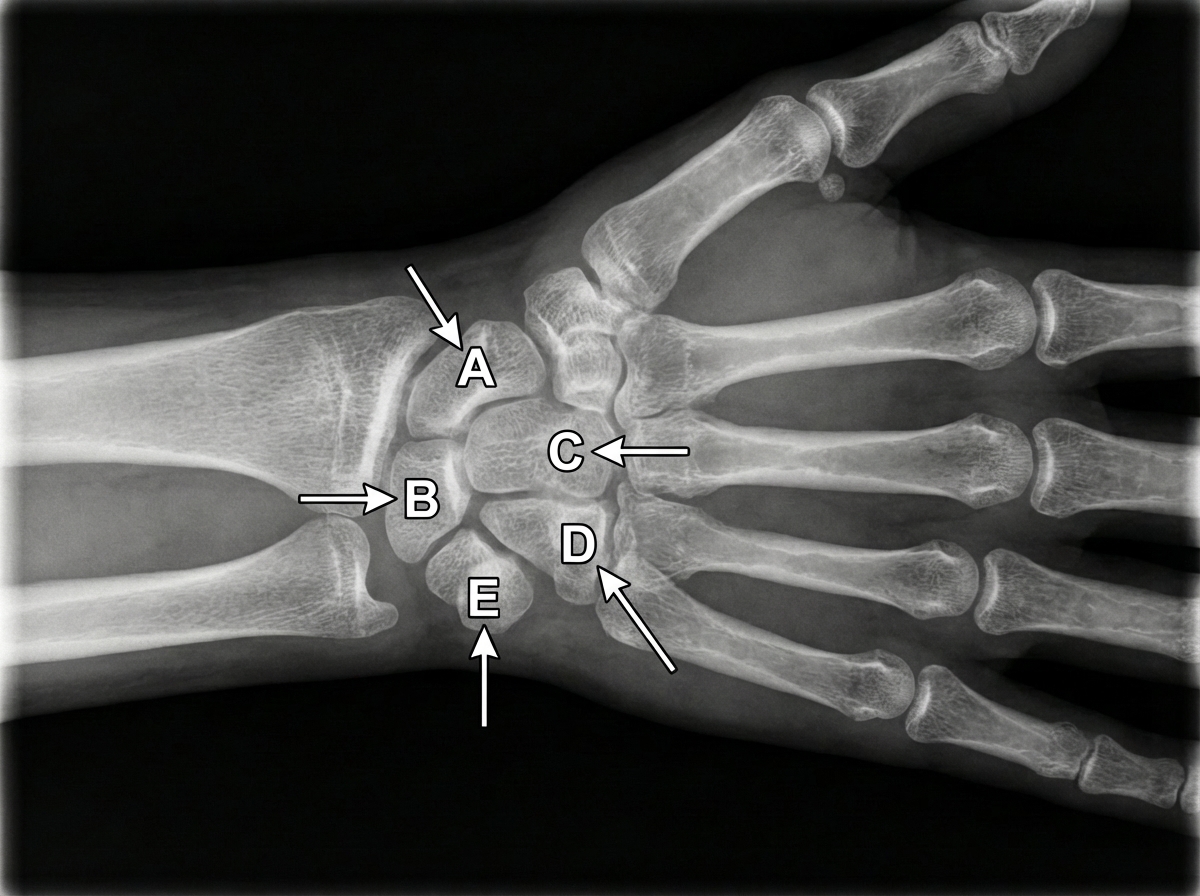

An X-ray of the wrist and hand is shown below. If there is damage to structure E, which of the following muscle weaknesses does it cause?

Explanation: ***Flexor carpi ulnaris*** - The **pisiform bone** (structure E) serves as the primary insertion point for the **flexor carpi ulnaris (FCU)**, which is innervated by the **ulnar nerve**. - Damage to the pisiform disrupts FCU function, causing weakness in **wrist flexion** and **ulnar deviation**, as FCU also inserts on the **hook of hamate** and **5th metacarpal base**. *Flexor carpi radialis* - Innervated by the **median nerve** and inserts on the base of the **2nd metacarpal**, not the pisiform bone. - Pisiform damage would not affect FCR function as it has no anatomical relationship with structure E. *Palmaris longus* - Innervated by the **median nerve** and inserts into the **palmar aponeurosis**, completely bypassing the pisiform bone. - This muscle's function remains intact with pisiform damage as it has no connection to structure E. *Brachioradialis* - Innervated by the **radial nerve** and inserts on the **distal radius**, not involving any carpal bones. - Pisiform bone damage has no impact on brachioradialis function due to its separate anatomical pathway and innervation.